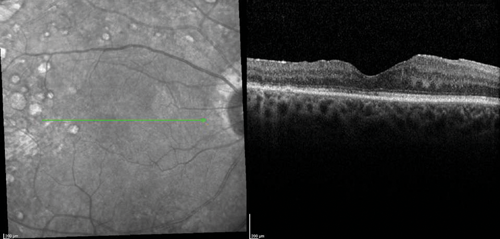

The clinical efficacy and safety of the drug have been also reported in two case reports of vitrectomised eyes with persistent DMO with both cases showing a desirable anatomical outcome. In one case, the authors have suggested that vitrectomy seemed to have enhanced the performance of the implant in-situ and achieved complete DMO resolution [19]. In a recently presented series of 20 post PPV eyes of 18 patients treated with Iluvien, a mean change of BCVA of +9 ETDRS letters (range -6 to +27) as well as mean reduction of CRT by -224µm (-595 to +126) were reported after a mean follow-up period of 201 days (range: 45 to 367 days) (SFO Paris 2016). Further real-life data of Iluvien in vitrectomised eyes with comparable clinical outcomes are awaited with interest. The author’s experience with the drug so far is in-keeping with published cases (Figure 1).

Figure 1 (d).

Figure 1: Case study for management of post-vitrectomy refractory DMO: (a) Pre-vitrectomy; (b) Post-vitrectomy; (c) Post six intravitreal anti-VEGF treatment with sub-optimal response; (d) Post-Iluvien one month. Complete resolution of DMO; (e) Post-Iluvien 10 months. Maintained response to treatment. (Courtesy of Mr David H W Steel - Sunderland Eye Infirmary).